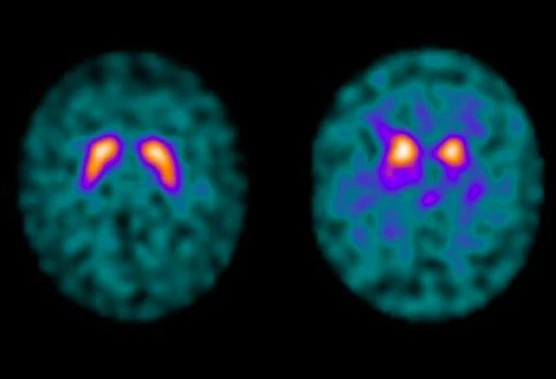

Für die Diagnosestellung führen wir eine ausführliche neurologische Untersuchung durch. Wir prüfen Beweglichkeit, Muskeltonus, Haltung und Gleichgewicht. Ergänzend können bildgebende Verfahren wie ein MRT durchgeführt werden; manchmal kommen auch nuklearmedizinische Untersuchungen wie ein DAT-Scan oder eine FDG-PET zum Einsatz, um die Diagnose zu sichern oder andere Ursachen auszuschließen.